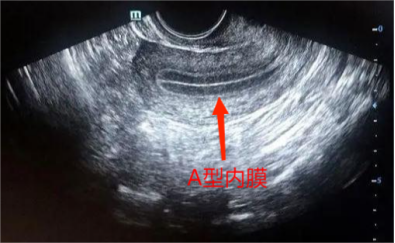

收录于合集#科普284个